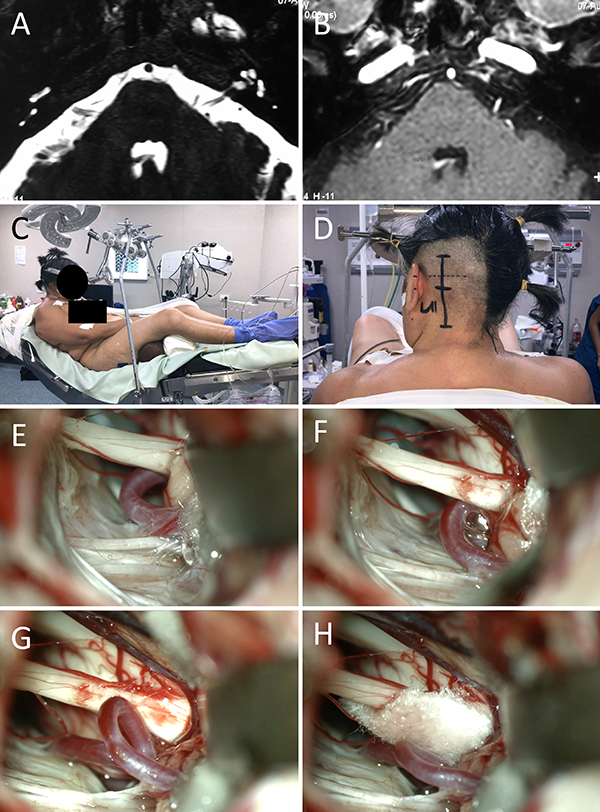

Figura 6:

Espasmo hemifacial, descompresiva PICA-Nervio facial. A-B: RM preoperatoria; C-D: Posición; E-H: Hallazgos intraoperatorios.

Figura 7:

Descompresiva neurovascular trigeminal. A-B: Posición; C-H: Hallazgos intraoperatorios, obsérvese el doble conflicto arterial (ACS) y venoso.